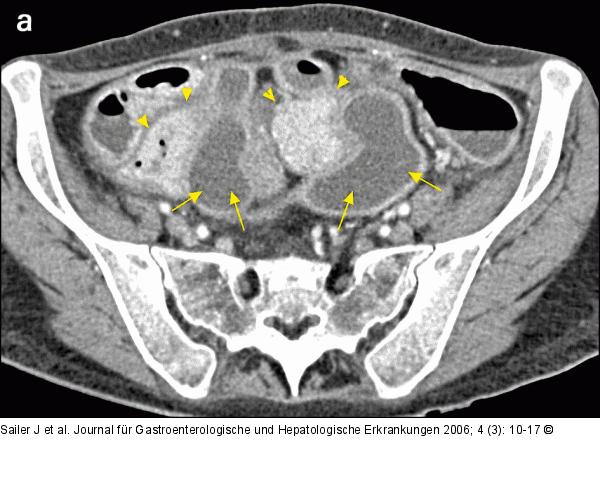

Abbildung 3a-b: CT-Enteroklysma CT-Enteroklysma einer 41jährigen Patientin, klinische Zeichen eines akuten Abdomens; axiale und coronale Rekonstruktionen: ausgedehnte, zwischen den Dünndarmschlingen gelegene Abszeßformation mit diskretem Rand-Enhancement (Pfeile), deutlich entzündliche Wandverdickung des terminalen Ileums (Pfeilspitzen). |

CT-Enteroklysma einer 41jährigen Patientin, klinische Zeichen eines akuten Abdomens; axiale und coronale Rekonstruktionen: ausgedehnte, zwischen den Dünndarmschlingen gelegene Abszeßformation mit diskretem Rand-Enhancement (Pfeile), deutlich entzündliche Wandverdickung des terminalen Ileums (Pfeilspitzen). |